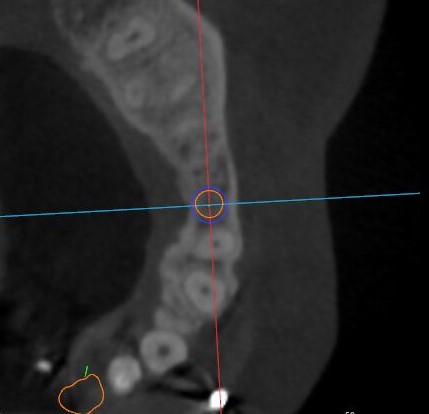

矢狀面視圖

根據(jù)患者CT顯示,使用種植導(dǎo)航軟件設(shè)術(shù)前手術(shù)方案??紤]到患者拒絕手術(shù)摘除上頜竇囊腫等因素,此次手術(shù)選用了Straumann骨水平4.10*8.0mm的植體,植體末端位點(diǎn)設(shè)計(jì)距上頜竇底壁2mm處的同時(shí)兼顧種植方向和修復(fù)間隙,來(lái)達(dá)到理想的效果。